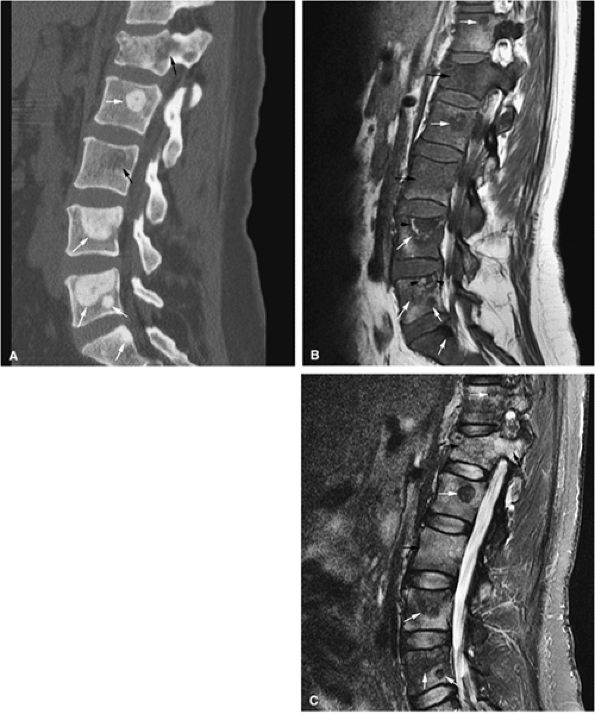

FIGURE 13.63 ● Metastatic breast carcinoma with osteo-blastic metastases. (A) Sclerotic metastases (white arrows) are seen on a sagittal CT image. Osteolytic marrow infiltration of the L1 vertebral body and posterior elements with an associated compression fracture is noted (black arrows). (B) Hypointense vertebral bodies are shown on a sagittal T1-weighted sagittal image (black arrows). The focal metastatic deposits are darker than the vertebral bodies (white arrows). Hyperintense signal surrounding the L4 and L5 metastases is noted, indicating response to therapy (arrowheads). (C) The osteoblastic lesions remain hypointense on a sagittal STIR image (white arrows), whereas the vertebral bodies are hyperintense (black arrows).

|